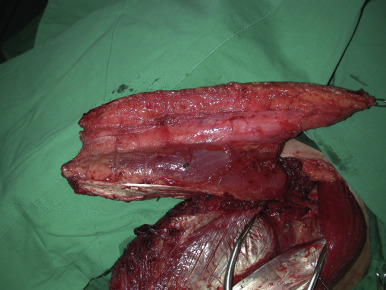

Subfascial Dissection ( Figs 59.5, 59.6, 59.7, 59.8 )

The medial incision is made down to and through the thigh fascia, exposing the rectus femoris muscle. The epimysium of this muscle is preserved and the dissection proceeds in a lateral direction until the septum separating the rectus femoris from the vastus lateralis is visualized ( Fig. 59.5 ). The entire septum is exposed by retracting the rectus femoris medially. At the medial aspect, the descending branch of the LCFA can be seen coursing over the vastus lateralis muscle ( Fig. 59.6 ). This exposure provides the operator with a map of the vascular anatomy of the region. Branches of the descending branch are observed either perforating the vastus lateralis muscle or traveling within the septum to reach the skin of the anterolateral aspect of the thigh. For septocutaneous vessels, the dissection is performed in a retrograde fashion and the vessel is dissected away from the surrounding tissues. If the skin vessel is a musculocutaneous perforator, then intramuscular dissection is performed in the following manner: the point of exit of the perforator is exposed and the muscle fibers anterior to the vessel are “lifted up” using teeth forceps; the tenotomy scissors are used to spread in a transverse plane over the perforator, and the muscle fibers are cut ( Fig. 59.7 ). This same series of steps is performed throughout the intramuscular course in a retrograde fashion. Small intramuscular branches, which generally arise from the lateral and posterior sides of the perforator and less commonly from the anterior side, are ligated. Perforator dissection proceeds until its take-off from the descending branch of the LCFA or further until adequate pedicle length is achieved ( Fig. 59.8 ). The main nerve and nerve branches supplying the vastus lateralis and the rectus femoris are carefully dissected away from the vessels and preserved.